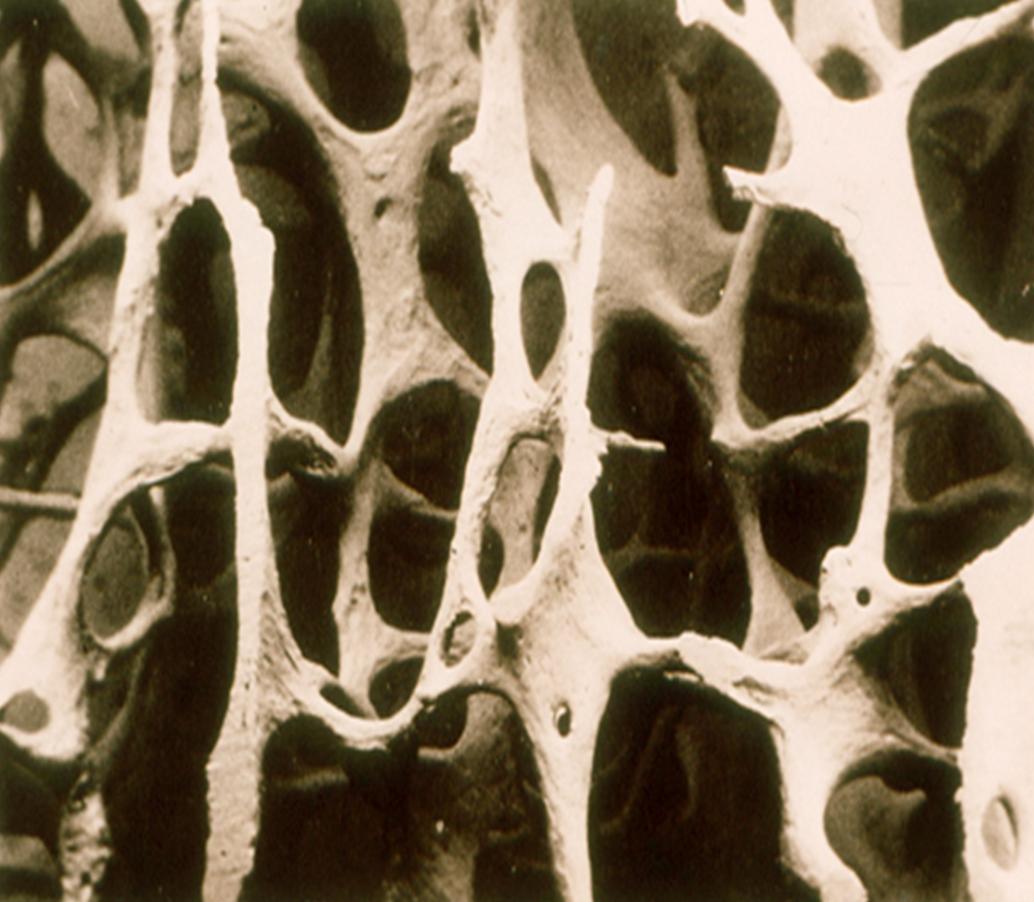

骨质疏松即为“多孔的骨头”。

如图所示,正常的骨骼是致密的。

由于各种原因,患上骨质疏松症,骨骼变得稀疏多孔,像年久失修的钢筋混凝土结构或者豆腐渣工程,轻微的外力就很容易使之坍塌。

(疏松的骨骼)

骨质疏松症的医学定义是指由于各种原因导致骨强度下降,即骨密度和骨质量下降,骨脆性增加,从而易于发生骨折的一种全身性骨骼疾病。